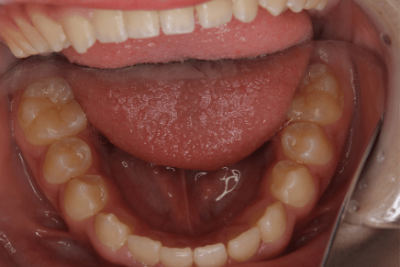

写真⑥:使用する装置例

写真⑦:使用する装置例